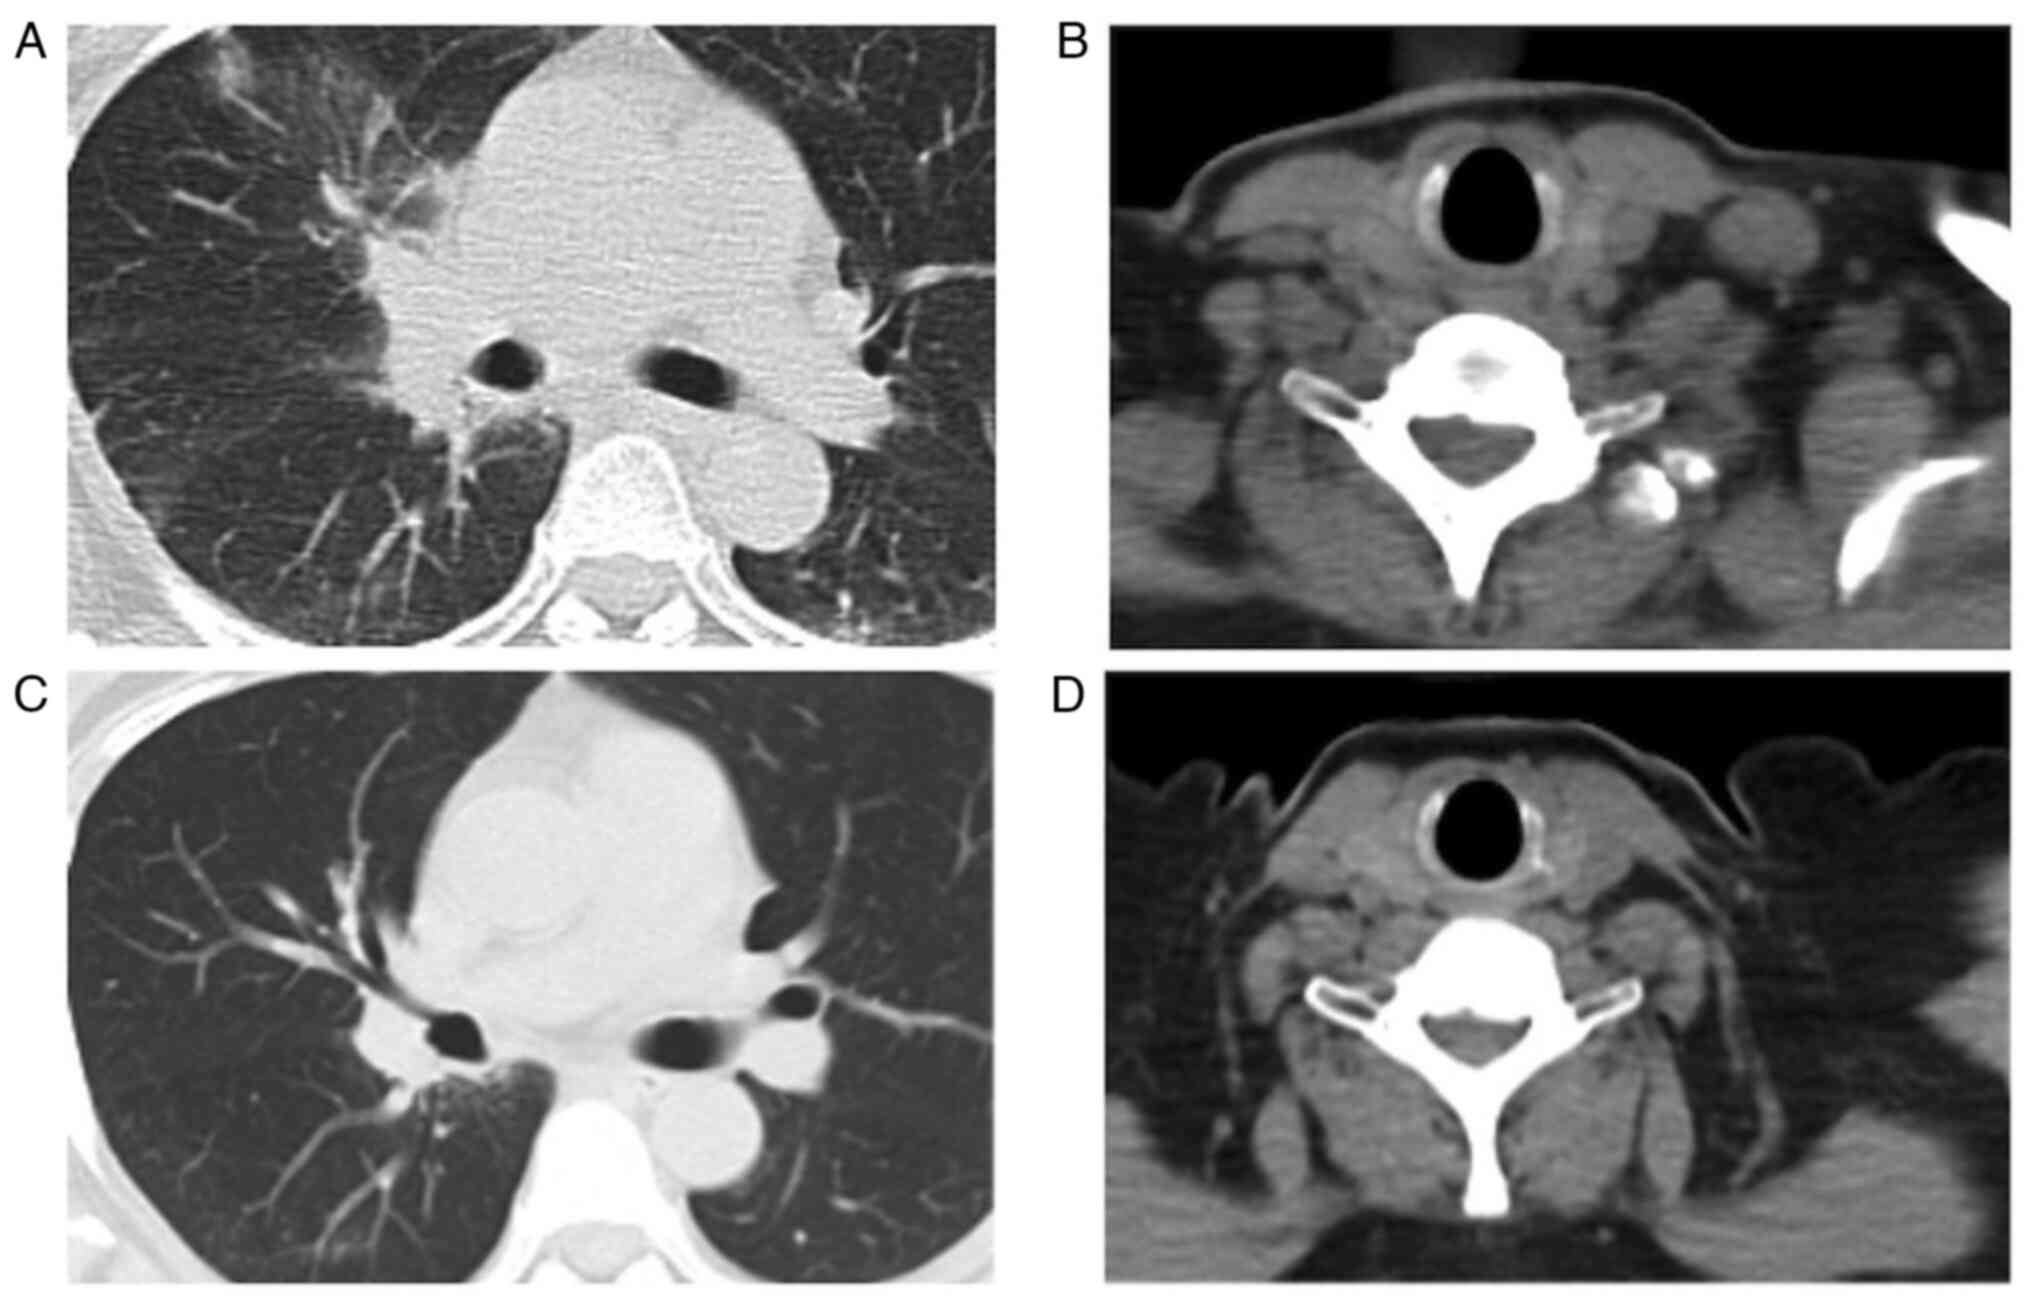

Figure 3.

Thoracic imaging findings at the start of crizotinib therapy and 16 months after crizotinib therapy. Chest CT scan showed (A) primary lung tumor in right upper lobe and (B) left supraclavicular lymphadenopathy at the start of crizotinib therapy. Chest CT scan showed (C) shrinkage of tumor in the right upper lobe and (D) disappearance of left supraclavicular lymphadenopathy at 16 months after crizotinib therapy. CT, computed tomography.